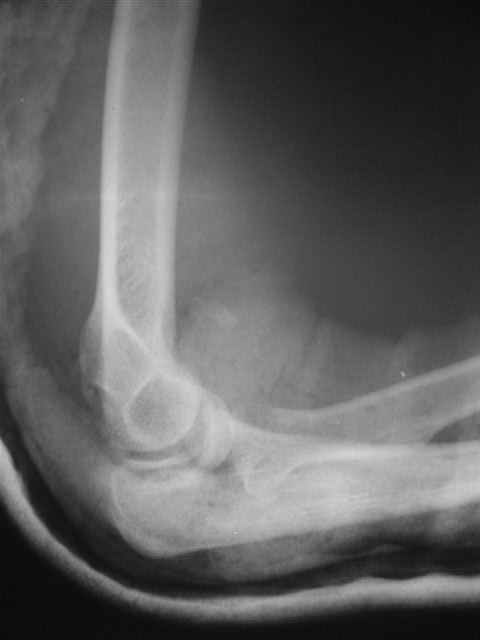

Вывих костей предплечья и перелом головки лучевой кости. |

Уважаемые коллеги!Помогите с источниками литературы по вопросу о сроках резекции головки лучевой кости и гетеротопической оссификации после вывиха костей предплечья. Необходимо ответить на жалобу, где больная просит возместитьматериальные затраты на лечения с лечащих врачей, которые участвовали влечении с 4.09.04 по 10.11.04, объясняет, что врачи нарушили стандарты леченияи поздно направили на оперативное лечение.История болезни, женщина 46 лет упала дома 4.09.04, получила заднелатеральныйвывих костей предплечья и перелом головки лучевой кости, под местной анестезиейвывих вправлен, на контрольной рентгенограмме соотношение отломков головкилучевой кости расценено, как удовлетворительное. Наложена задняя гипсовая шина.Лечение: холод, кетанов 3 дня, магнитотерапия, ЛФК пальцев, рентген контрольчерез 7 дней, с 8.09.05 наклофен 50 мг 2 раза в день. 11.09.04 на контрольной рентгенограмме состояние отломков прежнее. 30.09.04. Гипсовая шина снята через 26 дней. Лечение: ЛФК, массаж, электрофорезлидазой.9.10.04. В левом локтевом суставе сгибание 80, разгибание 120.19.10.04. Сгибание 80, разгибание 140, ротационные движения в пределах 10 гр.28.10.04. Сгибание 80, разгибание 150, ротационные движения в пределах 10 гр.10.11.04. На рентгенограмме локтевого сустава отмечается гетеротопическаяоссификация.Учитывая неэффективность консервативного лечения, больная направлена на оперативноелечение.Больная по собственным каналам уехала в г. Киев, где произведенарезекция головки лучевой кости, после операции развился неврит лучевого нерва.На данный момент больная продолжает лечение у нейрохирурга.-- С уважением,Анатолий Борзунов

Mozgounov> А есть снимки?

Во время встречи фотоаппарата не было, забрать снимки на время, муж больной снимки не разрешил.